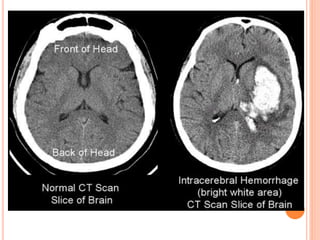

CT SCAN

 Mandatory initial investigation

 Haemorrhage appears instantly as a hyperdense

area

 Infarct appears as a hypodense area

 Infarct may not appear before 48 hrs

 MRI may be done instead but ct scan is more

sensitive for detecting haemorrhage

 Diffusion weighted MRI is good for identifying

ischaemic lesion.